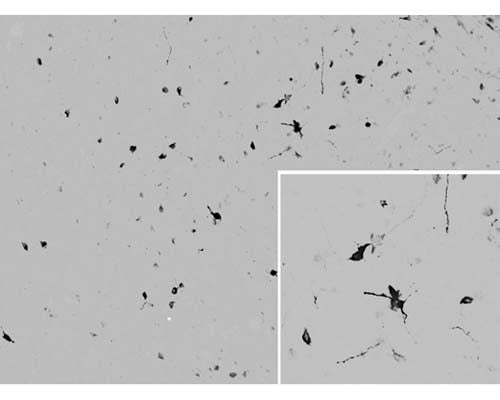

The cryostat section of the sheep hypothalamus was incubated in guinea pig polyclonal antibodies to the gamma melanocyte-stimulating hormone at the dilution of 1:1000 overnight followed by incubation with FITC- conjugated secondary antibodies. Cell bodies and nerve terminals in the sheep brain are intensely stained.